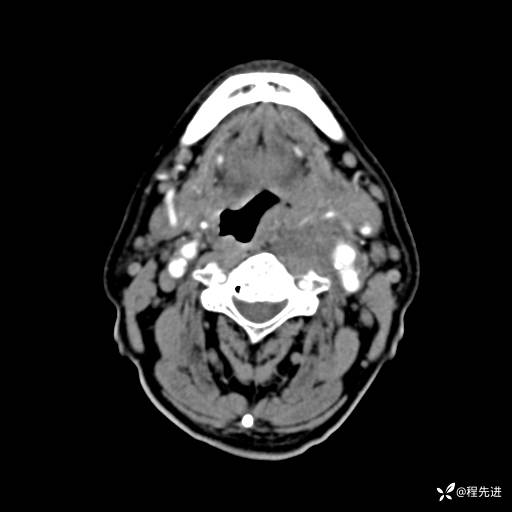

CT增强:

静脉期: